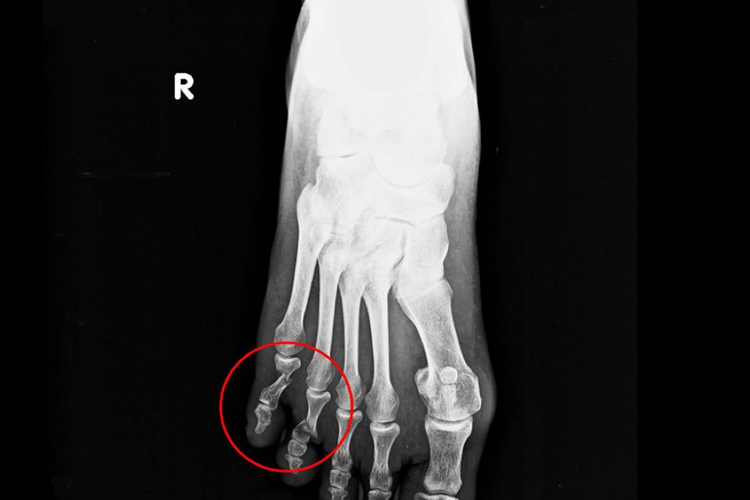

- 如果是稳定性骨折,经过妥善地固定和休息,二十天后骨折断端通常会有纤维连接形成,局部的炎症和肿胀逐渐减轻。此时,骨折部位的疼痛较受伤初期会有明显缓解,在不负重的情况下活动脚趾,可能只有轻微的疼痛或不适感。在X线检查中,可能会看到骨折线开始变得模糊,有少量骨痂开始形成,但骨折线仍可被观察到。

- 但如果骨折为粉碎性骨折、骨折断端有明显移位,或者患者没有严格遵循医嘱进行休息和固定,二十天后的恢复可能就不太理想。可能仍有较明显的肿胀和疼痛,骨折断端的纤维连接不牢固,骨痂形成较少甚至没有,骨折线依然清晰可见。